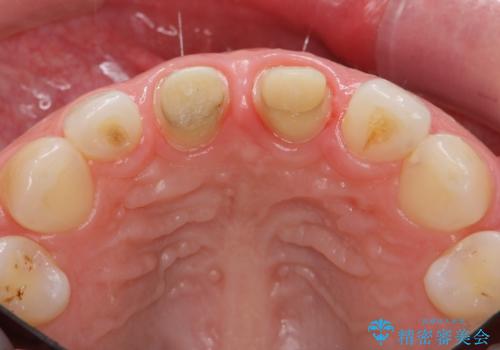

その後、マージンが舌側が深い状態だったため、歯ぐきの手術(歯周外科処置:APF)を行ってから最終的なセラミックを装着しました。

矯正治療前に、一旦、引っ込めた前歯の角度を元に戻してから(出っ歯の仮歯をもう一度つけました・・・!)矯正しました。

患者様には快くご協力いただき、しっかり口元を下げることができました。